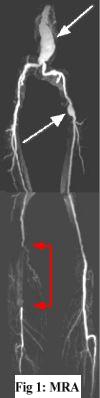

MRA FINDINGS: Fig. 1 on the left is the subtraction CE-MRA. Fig. 2 on the right displays selective x-ray angiogram images performed by Dr. Gadallah. There is a large fusiform aneurysm of the distal aorta and focal aneurysm in the left common femoral artery (white arrows), shown equally well on both MRA and x-ray angio (Fig. 2a). But the interesting finding is in the distal right superficial femoral artery (SFA) where there is 12 cm long segment occlusion seen on MRA (Fig. 1, red arrowheads) with reconstitution at the popliteal artery via collaterals. There is an apparent filling defect (arrows) within the SFA consistent with thrombosis. The surrounding hyperintensity probably represents enhancement in an edematous/inflamed vessel wall. The x-ray angio in Fig. 2b confirms total occlusion of distal SFA (blue arrows).